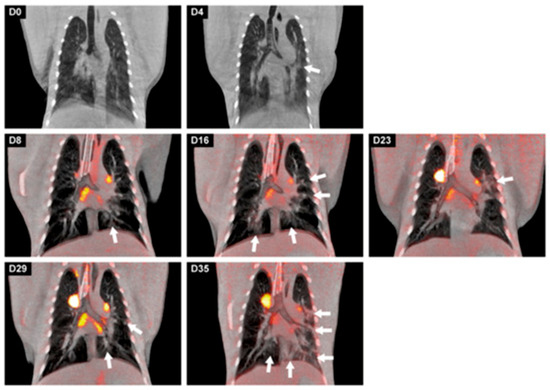

- Naninck, T.; Kahlaoui, N.; Lemaitre, J.; Maisonnasse, P.; De Mori, A.; Pascal, Q.; Contreras, V.; Marlin, R.; Relouzat, F.; Delache, B.; et al. Computed tomography and [18F]-FDG PET imaging provide additional readouts for COVID-19 pathogenesis and therapies evaluation in non-human primates. iScience 2022, 25, 104101. [Google Scholar] [CrossRef]